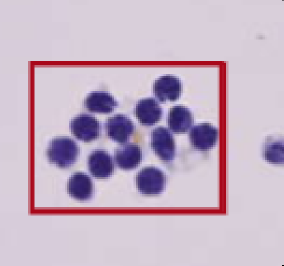

Identification Pattern

1. Normal tissue

2. Low & High grade

intraepithelial neoplasia

3. Adenocarcinoma

4. Signet ring cell carcinoma